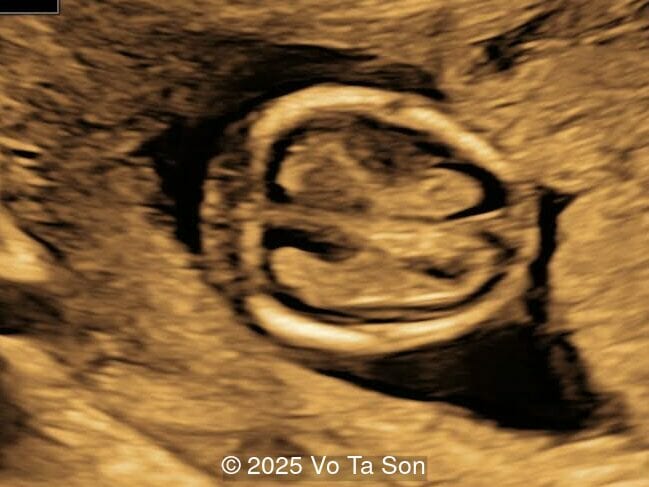

A woman underwent routine prenatal screening at 13 weeks. The non-invasive prenatal test (NIPT) showed low risk for common aneuploidies including trisomy 21, 18, and 13. However, first-trimester anomaly scan revealed multiple fetal anomalies.

We present a case of Triploidy with a 69,XXY chromosomal complement and open spina bifida in the first trimester.

Our imaging revealed the following significant fetal abnormalities:

• Open spina bifida in the sacral region with dry brain sign, crash sign, BS/BSOB >1, and a lesion at the sacral coccygeal spine. The spinal lesion observed in the sacral region is characterized by a posterior vertebral arch defect and a protruding meningeal sac.